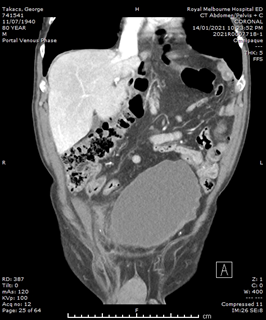

He had normal inflammatory markers, Hb 133g/L and Creatinine 104umol/L. A Computed Tomography (CT) scan of the abdomen and pelvis was performed, with the differentials considered being incarcerated inguinal hernia, diverticulitis or malignancy. However, the CT showed a 75mm, contained ruptured right internal iliac artery (IIA) aneurysm, with no active contrast extravasation (Figure 1). There was perianeurysmal haemorrhage in the right iliac fossa which extended into a small fat-containing inguinal hernia (Figure 2). There was also bladder distension and moderate-to-severe right hydroureteronephrosis secondary to the large aneurysm.

Figure 1 Arterial-phase CT images of the abdomen and pelvis. (A) Axial image showing the right internal iliac artery aneurysm with contained perforation and no contrast extravasation. (B) Coronal image showing the aneurysm exerting mass effect on bladder, and right sided hydronephrosis.